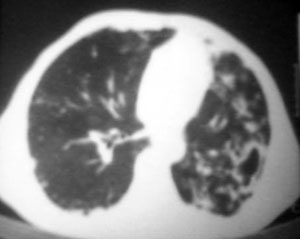

以下是引用逸风在2006-9-12 14:57:00的发言:[br]ct显示双肺上叶点片状及纤维索条状密度不均影,肺野外带近胸膜可见大小不等的含气空腔,壁略厚,境界清晰,未见液平面,中下肺野散在小片状及点状高密度影;纵隔内显示点状钙化,未见明显淋巴结肿大,构成胸廓诸骨未见明显异常.[br]诊断意见:1.双肺结核合并支气管播散;2.双肺上肺大泡.